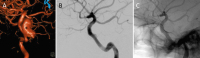

Neurovaskuläre Therapieoptionen bei komplexen Aneurysmen der Arteria carotis interna // Neurovascular therapeutic options in complex intracranial aneurysms

Journal für Neurologie, Neurochirurgie und Psychiatrie 2021; 22 (3): 128-134 Volltext (PDF) Summary Praxisrelevanz Abbildungen